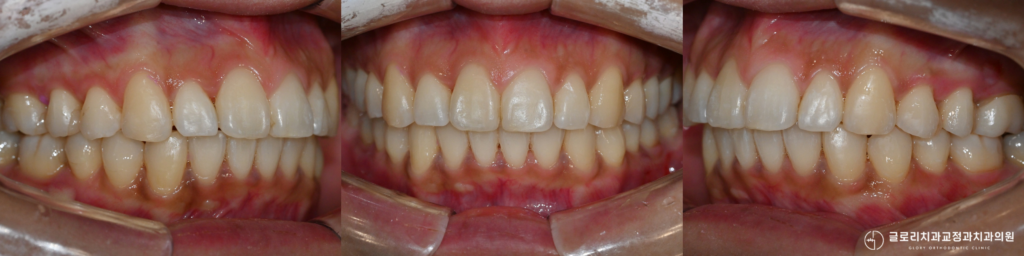

상악골확장이 이루어지면

입천장이 넓어지면서

치아가 배열될 공간이

자연스럽게 확보됩니다.

비발치 교정과 발치 여부 재평가

그러나 상악골확장을 먼저 진행하면

추가 공간이 생기기 때문에

발치 없이 치료가 가능해지는

경우가 있습니다.

치료기간 : 23.12.02 ~ 25.11.08